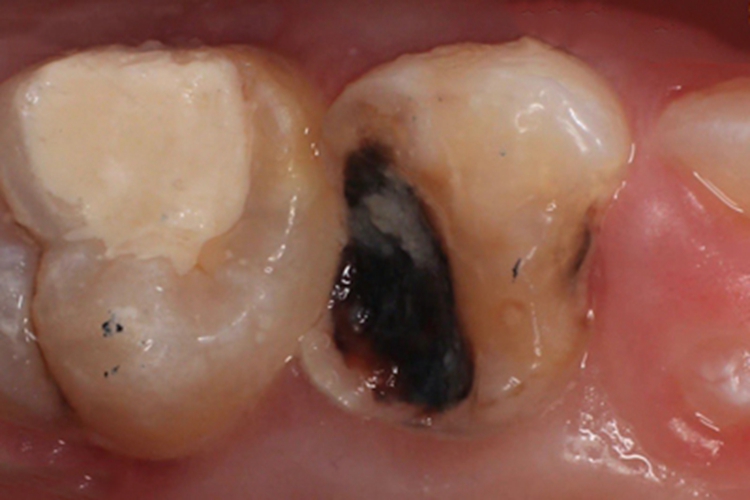

年轻恒牙龋的病变损害,常表现为局部出现黑斑,呈线状或点状,分布在牙齿表面的窝沟点隙上,同时牙齿硬组织缺损。常有食物残渣残留在凹陷处,常伴有牙齿疼痛难忍。